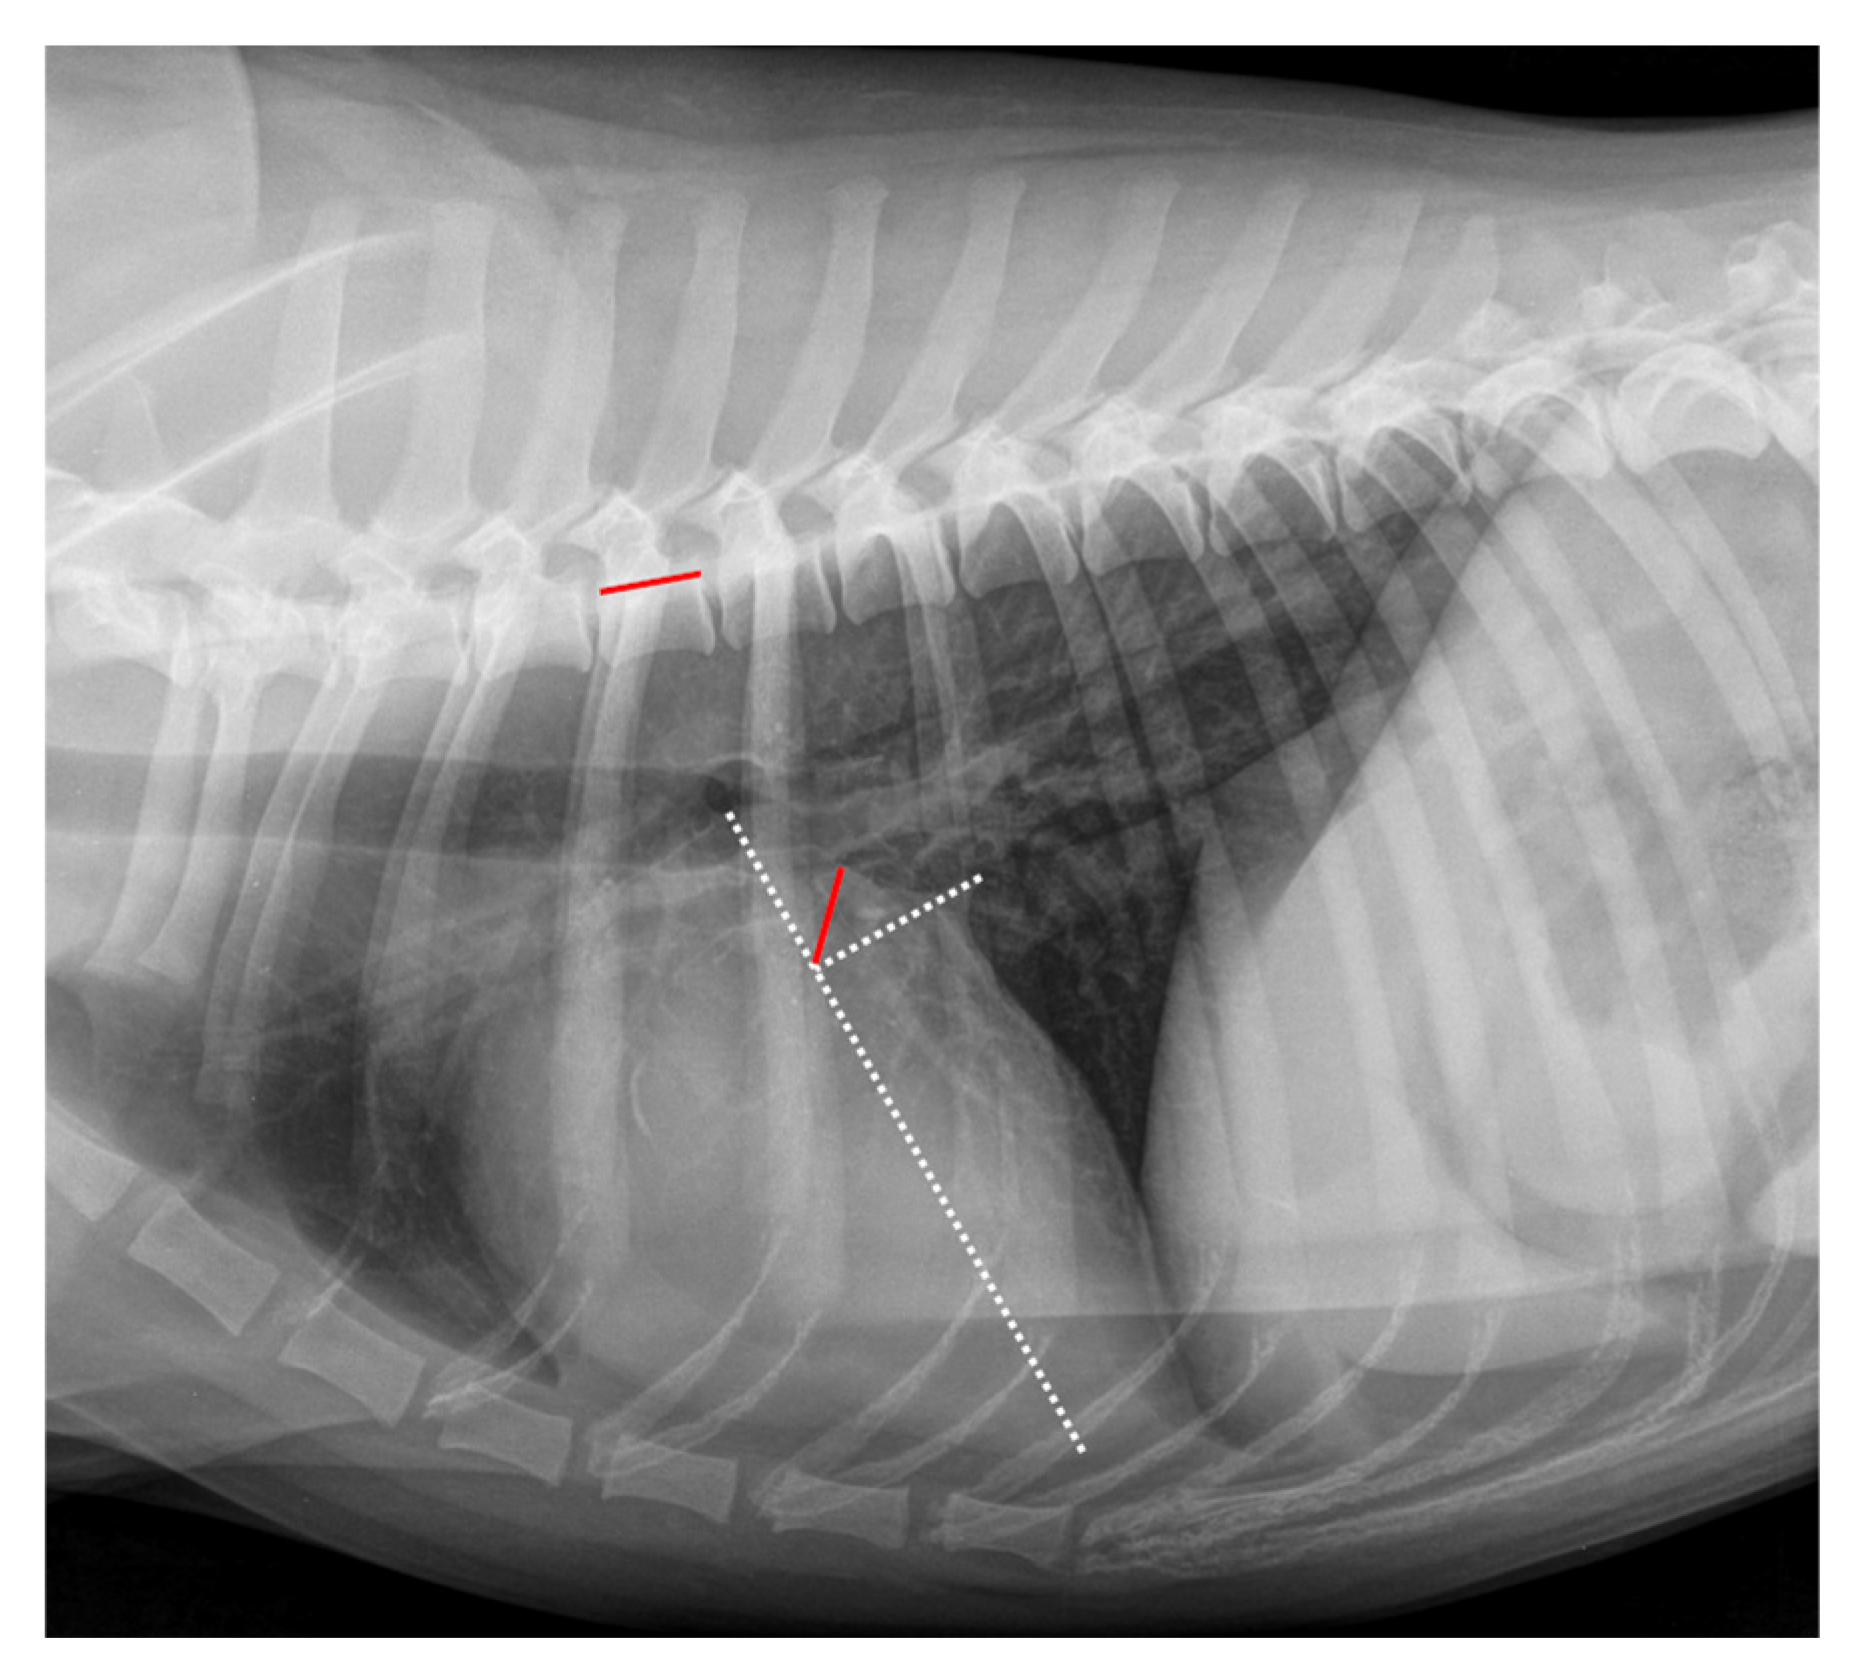

The RLAD was measured as described by Sanchez et al. (2018) [24]. An example of measurement is displayed in Figure 2. As a basis for measuring the RLAD, two axes had to be drawn similarly as described for the VHS. The long axis was drawn exactly as described for VHS. However, the short axis was drawn at the level of the dorsal intersection between the caudal vena cava and the cardiac silhouette and perpendicular to the long axis. Afterward, starting at the intersection point of the long and short axes, a bisecting line was drawn through the LA to its most dorsal margin. Finally, this line was transposed onto the cranial margin of the fourth thoracic vertebra, then the vertebral units were counted, and the result was recorded as RLAD.

Figure 2.

Radiographic Left Atrial Dimension (RLAD) measurement in the same right lateral thoracic radiograph seen in Figure 1. The long axis (white dotted line) was applied as described for the VHS measurement (Figure 1). The short axis (white dotted line) was drawn from dorsal intersection of the caudal vena cava and the cardiac silhouette to the long axis. The bisecting RLAD line was drawn from the intersection point to the dorsal margin of the left atrium (red line on cardiac silhouette). This line was transposed onto the vertebral column (red line on vertebral) as described in Figure 1. The RLAD was 0.8 vertebral units.